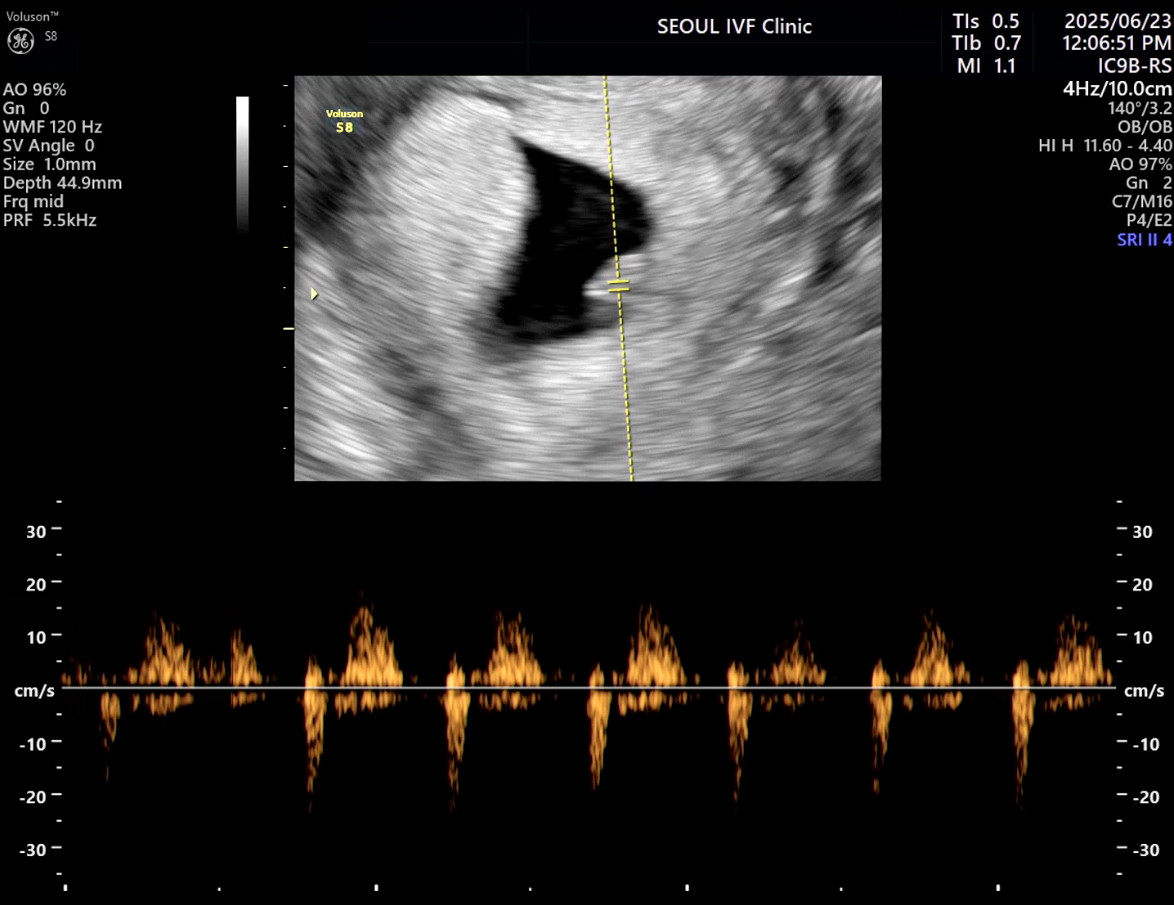

| 가슴 떨리는 임신 이야기를 공유해 주세요. | 몇 번의 실패로 절망적인 순간들을 겪었지만, 마침내 임신테스트기에 두 줄이 나온 순간은 지금도 잊을 수 없습니다. 특히 인공수정 1차에서 약간의 수치가 보여 잠시 기대했지만, 화학적 유산으로 끝나며 큰 좌절을 겪었습니다. 그러나 곧바로 이어진 시험관 1차에서 임신이 확인되었을 때, 그 기쁨은 말로 표현할 수 없을 만큼 벅찼습니다. |

| 치료 도중 느꼈던 가장 기뻤던 순간과 절망적인 것들은 무엇인가요? 잊지 못할 경험이 있나요? | 가장 기뻤던 순간은 역시 시험관 1차에서 임신이 확인되던 날이었습니다. 그날의 설렘과 감동은 평생 잊히지 않을 것 같습니다. 가장 절망적이었던 경험은 인공수정 1차에서 화학적 유산 판정을 받았을 때였습니다. 잠시나마 희망을 가졌던 만큼 무너지는 마음이 컸지만, 포기하지 않고 다시 도전했기에 결국 기적 같은 결과를 만날 수 있었습니다. |